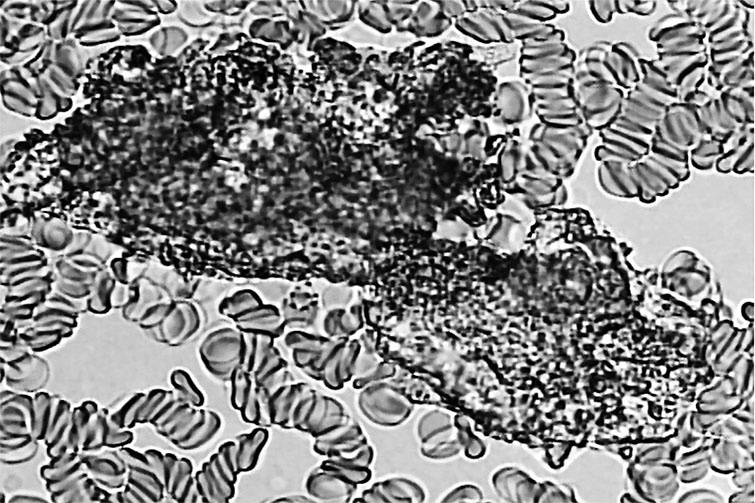

Давайте посмотрим на «неопознанного паразита» при большом увеличении и сравним с личинкой паразита, которую мы уже видели. ![]() Антенна-4 Что бросается в глаза? Личинка – гладкая, гибкая, без каких-либо выступов и узлов, приспособленная для передвижения в стесненных условиях. А «неопознанный паразит» весь покрыт длинными выростами, которые наверняка будут затруднять его продвижение. Кроме того, у личинки можно без труда определить, где вход в кишечный тракт (рот), а где из него выход (не рот). У волосатого чудища ни первое, ни второе найти не получается. Да и размеры просто гигантские: такое не то что в капилляры – не в каждую вену поместится. Итак, как и в примере с личинкой паразита, мы имеем дело со срежиссированным артефактом. Нечто таких размеров и очертаний через прокол в подушечке пальца не сможет выбраться ни при каких условиях, то есть наблюдаемое в микропрепарате привнесено извне. И в данном случае можно точно установить, что это и откуда оно взялось. Помните, мы говорили о том, что гемосканирование обычно проходит в не приспособленных для этого помещениях, грязных с точки зрения требований к клинической лаборатории? Так вот, «неопознанный паразит» попал в каплю крови из воздуха, и на самом деле это обломок хитиновой антенны комара-звонца. На фотографии с сайта Университета Мичигана очень хорошо видно сходство. ![]() Комар-звонец Кристаллы В нашем организме действительно могут образовываться кристаллы. Чаще всего в моче, но и в крови они иногда встречаются. Например, игольчатые кристаллы уратов (солей мочевой кислоты) при подагре. Их можно увидеть после определенной подготовки (фиксация, окраска) [62] препарата крови, однако при гемосканировании их почему-то обнаруживают и в живой капле, причем в очень интересном виде. ![]() Мочевая кислота Ну да, некая игольчатость присутствует, края острые, похожие на осколки… Постойте, но ведь это и есть осколки! Присмотритесь, отлично видно, что стекло треснуло в центре от давления сверху. Так происходит, когда неопытные лаборанты или студенты слишком быстро выкручивают винт, приближающий объектив микроскопа к предметному столику. Линза сначала упирается в лежащее сверху препарата тонкое покровное стекло, а затем раздавливает его с характерным грустным хрустом. Кроме того, попадаются особенно сильные уникумы, умудряющиеся сломать таким манером и куда более толстое предметное стекло, на которое наносится капля крови или образец другой ткани. Впрочем, в атласе встречаются и более экзотические примеры. Вот, скажем, кристаллы ортофосфорной кислоты. ![]() Ортофосфорная кислота Этим микропрепаратом рекомендуется пугать подростков, любящих пепси или кока-колу. Не знаю, как такое зрелище действует на неокрепшие детские умы, но у человека, имеющего большой опыт работы с микроскопом и обладающего познаниями в клинической лабораторной диагностике, оно вызывает лишь смех. Во-первых, ортофосфорная кислота прекрасно растворяется в воде [63], и с 1952 года, которым датирован указанный в сноске справочник, ровным счетом ничего не изменилось. Во-вторых, кристаллизуются ее полугидраты, и итоговые кристаллы получаются белого цвета, а не черного. В-третьих, для кристаллизации при температуре тела требуется настолько высокая насыщенность раствора [64], что это должна быть кровь Чужого, а не человека. В-четвертых, если присмотреться, можно заметить, что черное пятно находится на переднем плане, то есть не внутри крови, а как бы перед ней. И это ощущение абсолютно правильное. С подобными «кляксами» сталкивались многие лаборанты: это самая обычная грязь на линзе объектива. С «кристаллами сахара», которые, по мнению составителей атласа, запечатлены на следующей фотографии, история примерно та же. ![]() Кристаллы сахара Во-первых, «сахара» в крови нет. Основной простой углевод нашего организма – моносахарид глюкоза. И авторам якобы медицинского издания неплохо бы это знать. Во-вторых, глюкоза в той концентрации, в которой она присутствует в крови, и при температуре тела кристаллизоваться не может [65], ей запрещают это делать законы химии и физики. Вспомните, когда засахаривается мед или варенье. Приблизительно столько же «сахара» должно быть и в крови. Холестерин Вообще-то в соответствии с химической номенклатурой этот жирный спирт положено называть холестеролом, но, чтобы вы, уважаемые читатели, окончательно не запутались, воспользуемся устоявшимся в русском языке, хотя и некорректным термином. Вот так, по мнению авторов атласа, выглядит под микроскопом холестерин. ![]() Холестерин |